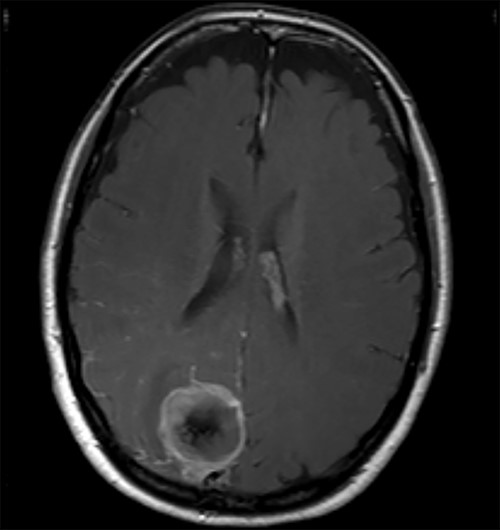

Two weeks later, whilst awaiting surgery, she attended the Emergency Department with a fever of 38.6°C and mildly raised inflammatory markers (WCC 10.4, Neut 8.4). Urine dip and CXR were unremarkable. The source of the infection was not isolated and the emergency medicine physicians discharged her with a course of empirical oral antibiotics. The neurosurgical team were not made aware of this attendance. Twelve days later, she underwent a planned neuronavigation-planning MRI scan as an outpatient. This was arranged one week prior to the scheduled surgery, in line with our departmental protocol. The MRI was reviewed and two new rim-enhancing collections superior and inferior to the tumour were noted, associated with extensive perilesional oedema (Fig. 2A and B). The patient was then immediately contacted via telephone and reported new worsening of headaches and new right sided weakness. She was admitted to hospital directly for assessment and emergency treatment. Her inflammatory markers on admission had risen to a WCC of 19.5, Neut 16.6, but CRP was <1. She was started on an emergency steroid treatment and subsequently underwent craniotomy, total resection of the meningioma and drainage of the intraparenchymal paratumoural abscesses. Intra-operatively the brain was swollen; pus collections were encountered in abscess cavities superior and inferior to the solid tumour, which had a necroticcore.

T1 weighted MRI postgadolinium enhancement in both sagittal (A) and coronal (B) views. There are two new rim-enhancing cystic lesions. A superior lesion of 31.4 mm as measured on the coronal reconstructed images and is abutting the adjacent dura of the right parietal lobe and is sited superior and lateral to the right occipital lesion. Another lesion sited inferior to the known right occipital lesion is the larger of the two lesions and has a septation within it. This measures approximately 34.4 mm on the coronal reconstructed images. On the sagittal images, it can be seen that the anterosuperior enhancing border of this lesion has a thicker and more ill-defined age. There is an adjacent vasogenic oedema.